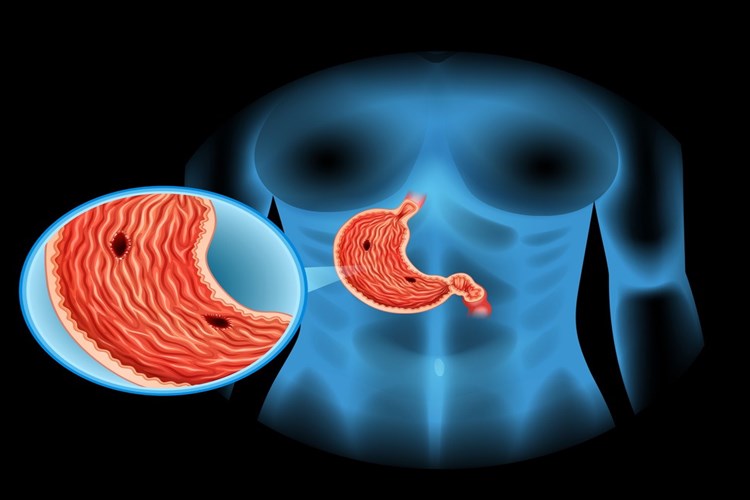

Bal Ülsere İyi Gelir Mi?

Bal, arıların nektarından veya bitki özlerinden topladığı ve

işlediği bir tatlı gıdadır. Bal, karbonhidratların çoğunu (örneğin glikoz ve

früktoz) içerir ve ayrıca su, vitaminler, mineraller ve antioksidanlar gibi

diğer besin öğeleri içerir. Bal, ülser hastalarına yardımcı olabilecek doğal

bir besindir. Bal, antioksidan özelliklere sahip olduğu için mide ülserlerinde

oluşan serbest radikallerle mücadele edebilir. Ayrıca, antibakteriyel

özellikleri nedeniyle Helicobacter pylori adlı bakterinin büyümesini

engelleyebilir. Ancak, balın ülser tedavisindeki etkisi sınırlıdır ve yalnız

başına kullanılmamalıdır.